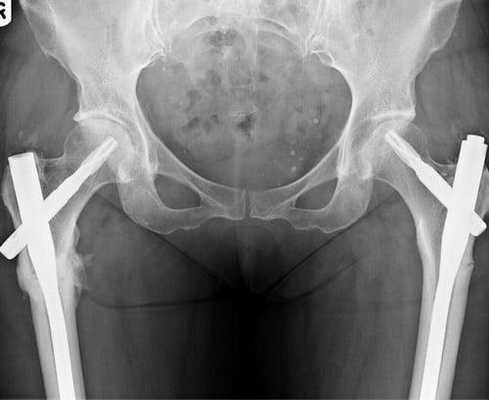

Остеосинтез с помощью гамма-стержня

Одна из операций выбора для внутреннего (интрамедуллярного) остеосинтеза - фиксация отломков при помощи гамма-стержня.

Основная идея блокированного интрамедуллярного остеосинтеза (БИОС) гамма-стержнем заключается в уменьшении, по сравнению с другими интрамедуллярными конструкциями, расстояния от центра оси механической нагрузки, расположенного в теле бедренной кости, до центра вращения бедра, коим является головка этой кости. Эта особенность значительно снижает нагрузку на протез и повышает надежность его фиксации.

Применение гамма-штифтов

Остеосинтез при помощи гамма-гвоздя применяется для фиксации следующих видов переломов бедренной кости в проксимальной (вертельной) ее части

- Подвертельные

- Межвертельные

- Чрезвертельные

- Медиальные и латеральные переломы шейки бедренной кости

- Полифрагментарные переломы бедра в вертельно-подвертельной области